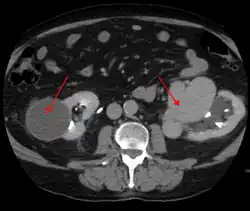

AVMs are diagnosed primarily by the following imaging methods:[12]

- Computed tomography (CT) scan is a noninvasive X-ray to view the anatomical structures within the brain to detect blood in or around the brain. A newer technology called CT angiography involves the injection of contrast into the blood stream to view the arteries of the brain. This type of test provides the best pictures of blood vessels through angiography and soft tissues through CT.

- Magnetic resonance imaging (MRI) scan is a noninvasive test, which uses a magnetic field and radio-frequency waves to give a detailed view of the soft tissues of the brain.

- Magnetic resonance angiography (MRA) – scans created using magnetic resonance imaging to specifically image the blood vessels and structures of the brain. A magnetic resonance angiogram can be an invasive procedure, involving the introduction of contrast dyes (e.g., gadolinium MR contrast agents) into the vasculature (circulatory system) of a patient using a catheter inserted into an artery and passed through the blood vessels to the brain. Once the catheter is in place, the contrast dye is injected into the bloodstream and the MR images are taken. Additionally or alternatively, flow-dependent or other contrast-free magnetic resonance imaging techniques can be used to determine the location and other properties of the vasculature.